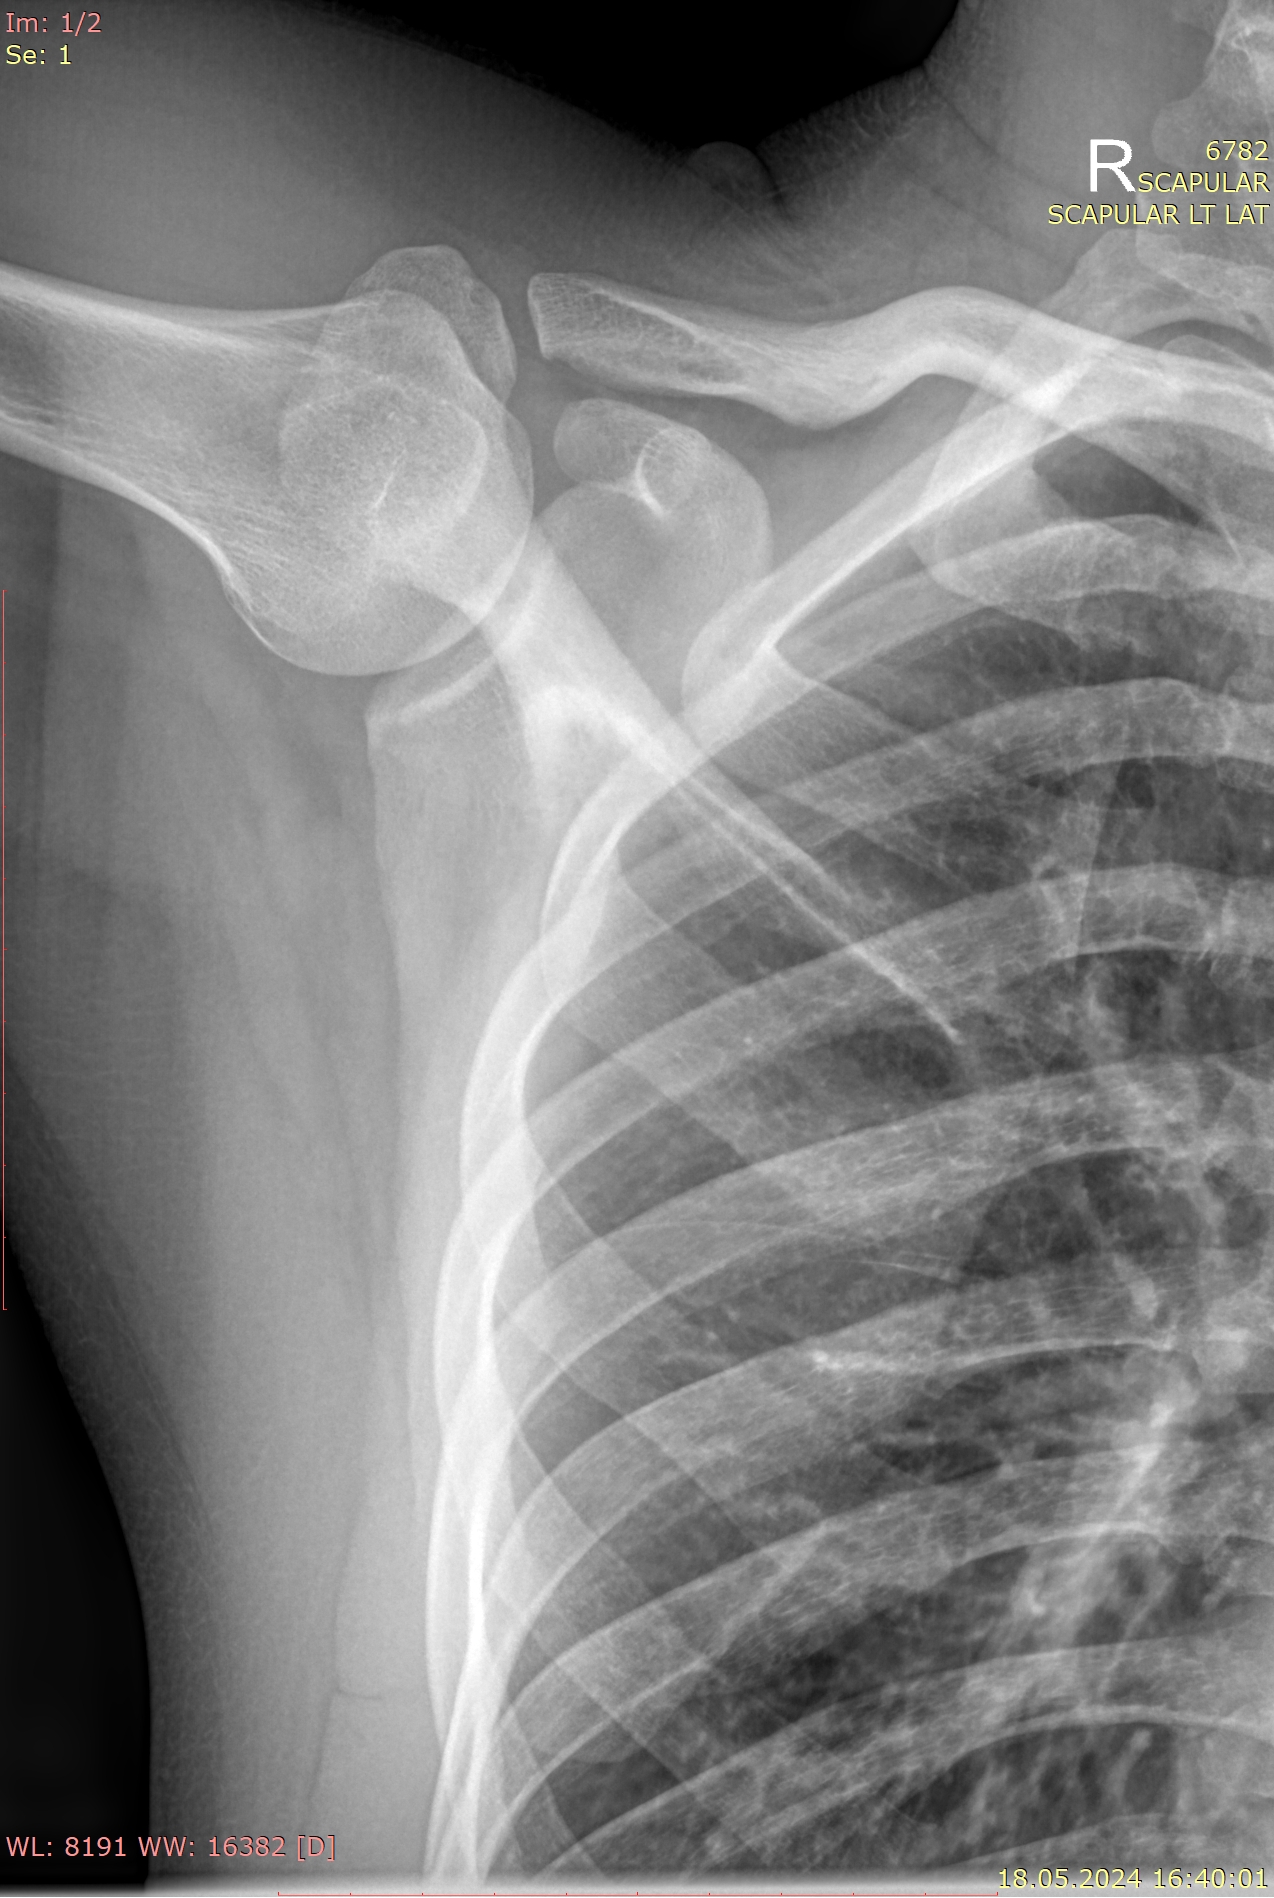

Лопатка ― плоская парная кость, играющая важную роль в креплении верхней конечности к туловищу. При патологиях лопатки, как и любой другой кости, в качестве первичного исследования используют рентгенографию. Этот метод исследования основан на способности органов по-разному поглощать рентгеновское излучение. Костная ткань, как наиболее плотное образование тела, поглощает больше всего х-лучей и на снимке кости выглядят светлыми.. Линии переломов выглядят темными трещинами, а новообразования имеют отличную от нормальной структуру.

В целом перелом лопатки встречается крайне редко: во-первых, она довольно прочная, а во-вторых удачно «лежит» сзади на грудной клетке, и надо еще постараться так упасть, чтобы ее сломать, или получить сильный прямой удар. В тяжелом случае переломы бывают осколочными и им часто сопутствует вывих плеча.

• Состояние костной ткани лопатки: перелом, новообразования, очаги некроза;

• Местоположение лопатки относительно других костей;

• Состояние суставных щелей сочленений, попавших на снимок;

• Состояние мягких тканей, инородные тела.

• Для прямого снимка важно плотно прижать исследуемую лопатку к пластине детектора, руками при этом упираются в бока или кладут на голову. По команде рентгенолаборанта в момент съемки необходимо на 1-2 секунды замереть и не дышать;

• Для бокового пациент поворачивается исследуемым боком к пластине или ложится на бок, также убирая руки из зоны фокуса. Съемка проходит аналогично.